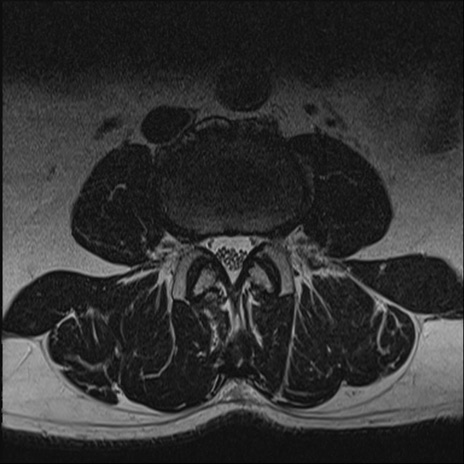

【整形】TIPS症例2 腰椎MRI T2WI(横断像)

【症例】70歳代男性

【主訴】左下肢痛

【現病歴】2週間前くらいから腰痛、左下肢痛あり。左臀部から大腿、下腿外側のしびれが常時ある。歩行とともに同部位の痛みあり。

【身体所見】Lasegue70-/60+、Bragard-/±、PTR ±/±、ATR -/-、IP 5/5、TA 5/4、TS 5/5、EHL 右第1足趾なし/3、FHL 5/5、hypersthesia(-)、足背動脈触知良好

異常所見と診断は?